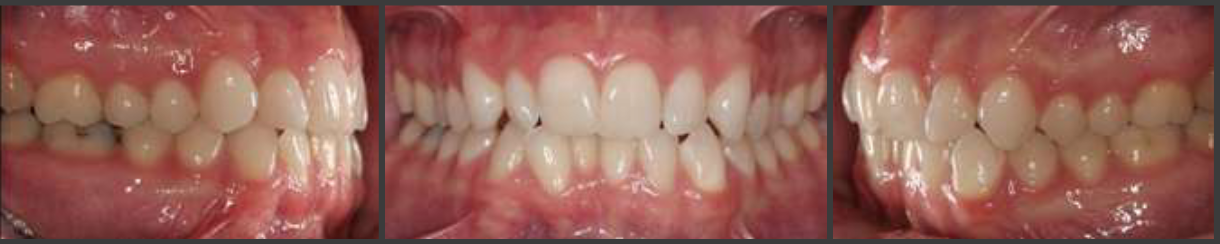

straight/orthognathic

how would you classify this profile

concave

prognathic

in a CONCAVE profile the MANDIBULAR jaw is

how would you class this occlusion